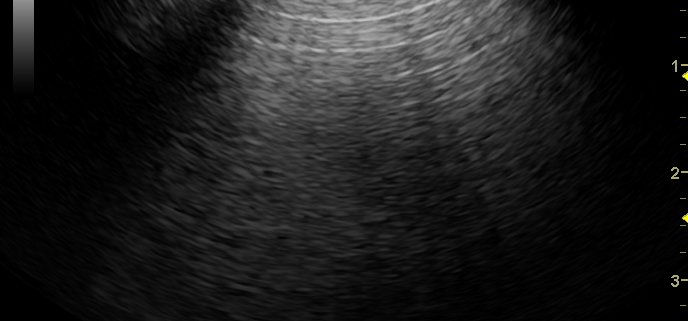

Portografía normal y portografía de shunt portosistémico intrahepático. En el primer video puede verse como el contraste administrado en la vena mesentérica llega al hígado poniendo de manifiesto la ausencia de shunt